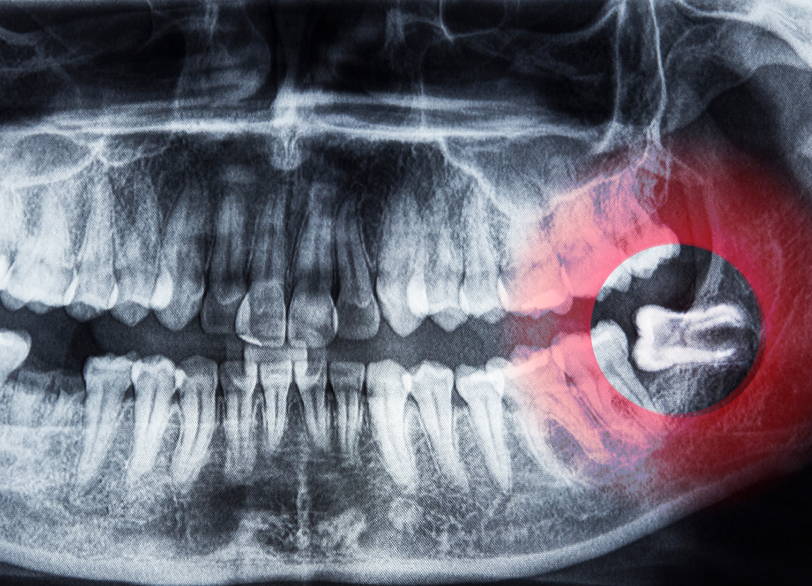

こだわり1:CTによる精密な術前診断

特に下顎の親知らずの抜歯において最も注意すべき合併症の一つが、歯の根の近くを通っている太い神経(下歯槽神経)の損傷による麻痺です。

当院では、安全な抜歯を行うために、必要に応じてデンタルCT撮影を行います。

CTを用いることで、従来のレントゲンでは分からなかった親知らずの根の形態や位置、そして神経管との三次元的な位置関係を正確に把握することができます。

これにより、神経損傷のリスクを事前に評価し、それを回避するための最適な抜歯計画を立てることが可能になります。まさに「急がば回れ」で、安全な手術のためには不可欠な検査です。

- 骨の中に完全に埋まっている親知らず(完全埋伏智歯)

- 横向きに倒れている親知らず(水平埋伏智歯)

- 歯の根が曲がっていたり、神経に近接していたりする親知らず

など、抜歯の難易度が高いとされるケースについても、当院での対応が可能な場合があります。 CTによる精密な診断と、マイクロスコープなどを用いた高度な技術を駆使し、安全性を確保しながら抜歯を行います。 実際に、他の歯科医院で抜歯が難しいと判断された患者様や、大学病院からご紹介いただくケースも少なくありません。